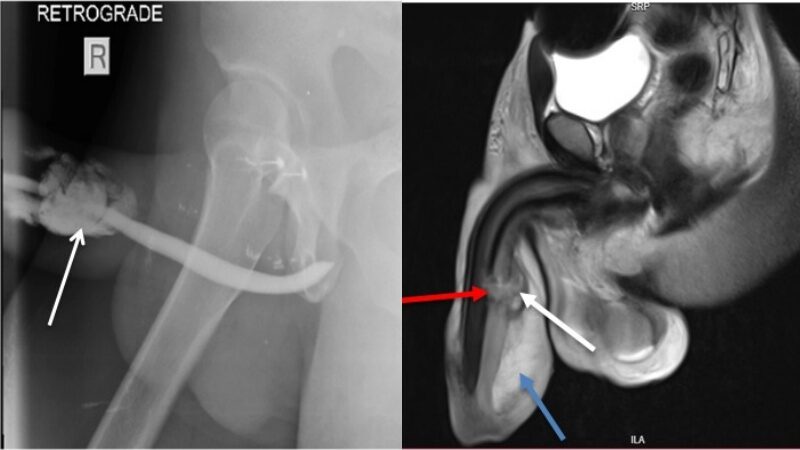

ผลการตรวจด้วยคลื่นแม่เหล็กไฟฟ้า เผยให้เห็นว่าชายคนนี้ได้รับบาดเจ็บที่อวัยวะเพศของเขาใน 3 จุดตามแนวทูนิกา อัลบูจิเนีย (เนื้อเยื่อเส้นใยที่ทำหน้าที่ปกคลุมอัณฑะในร่างกายของเนื้อเยื่อแข็งตัว) ที่เรียกว่า คอร์โปรา คาเวอร์โนซส (corpora cavernosa:เนื้อเยื่อเกี่ยวกับการแข็งตัว) และในอีกบริเวณหนึ่งที่เรียกว่า คอร์ปุส คาเวอร์โนซุม (corpus spongiosum: เนื้อเยื่อพรุน อ่อนนิ่มและยืดหยุ่นคล้ายฟองน้ำ ห่อหุ้มท่อปัสสาวะ)

องคชาตหัก

ภาพจาก International Journal of Surgery Case Reports